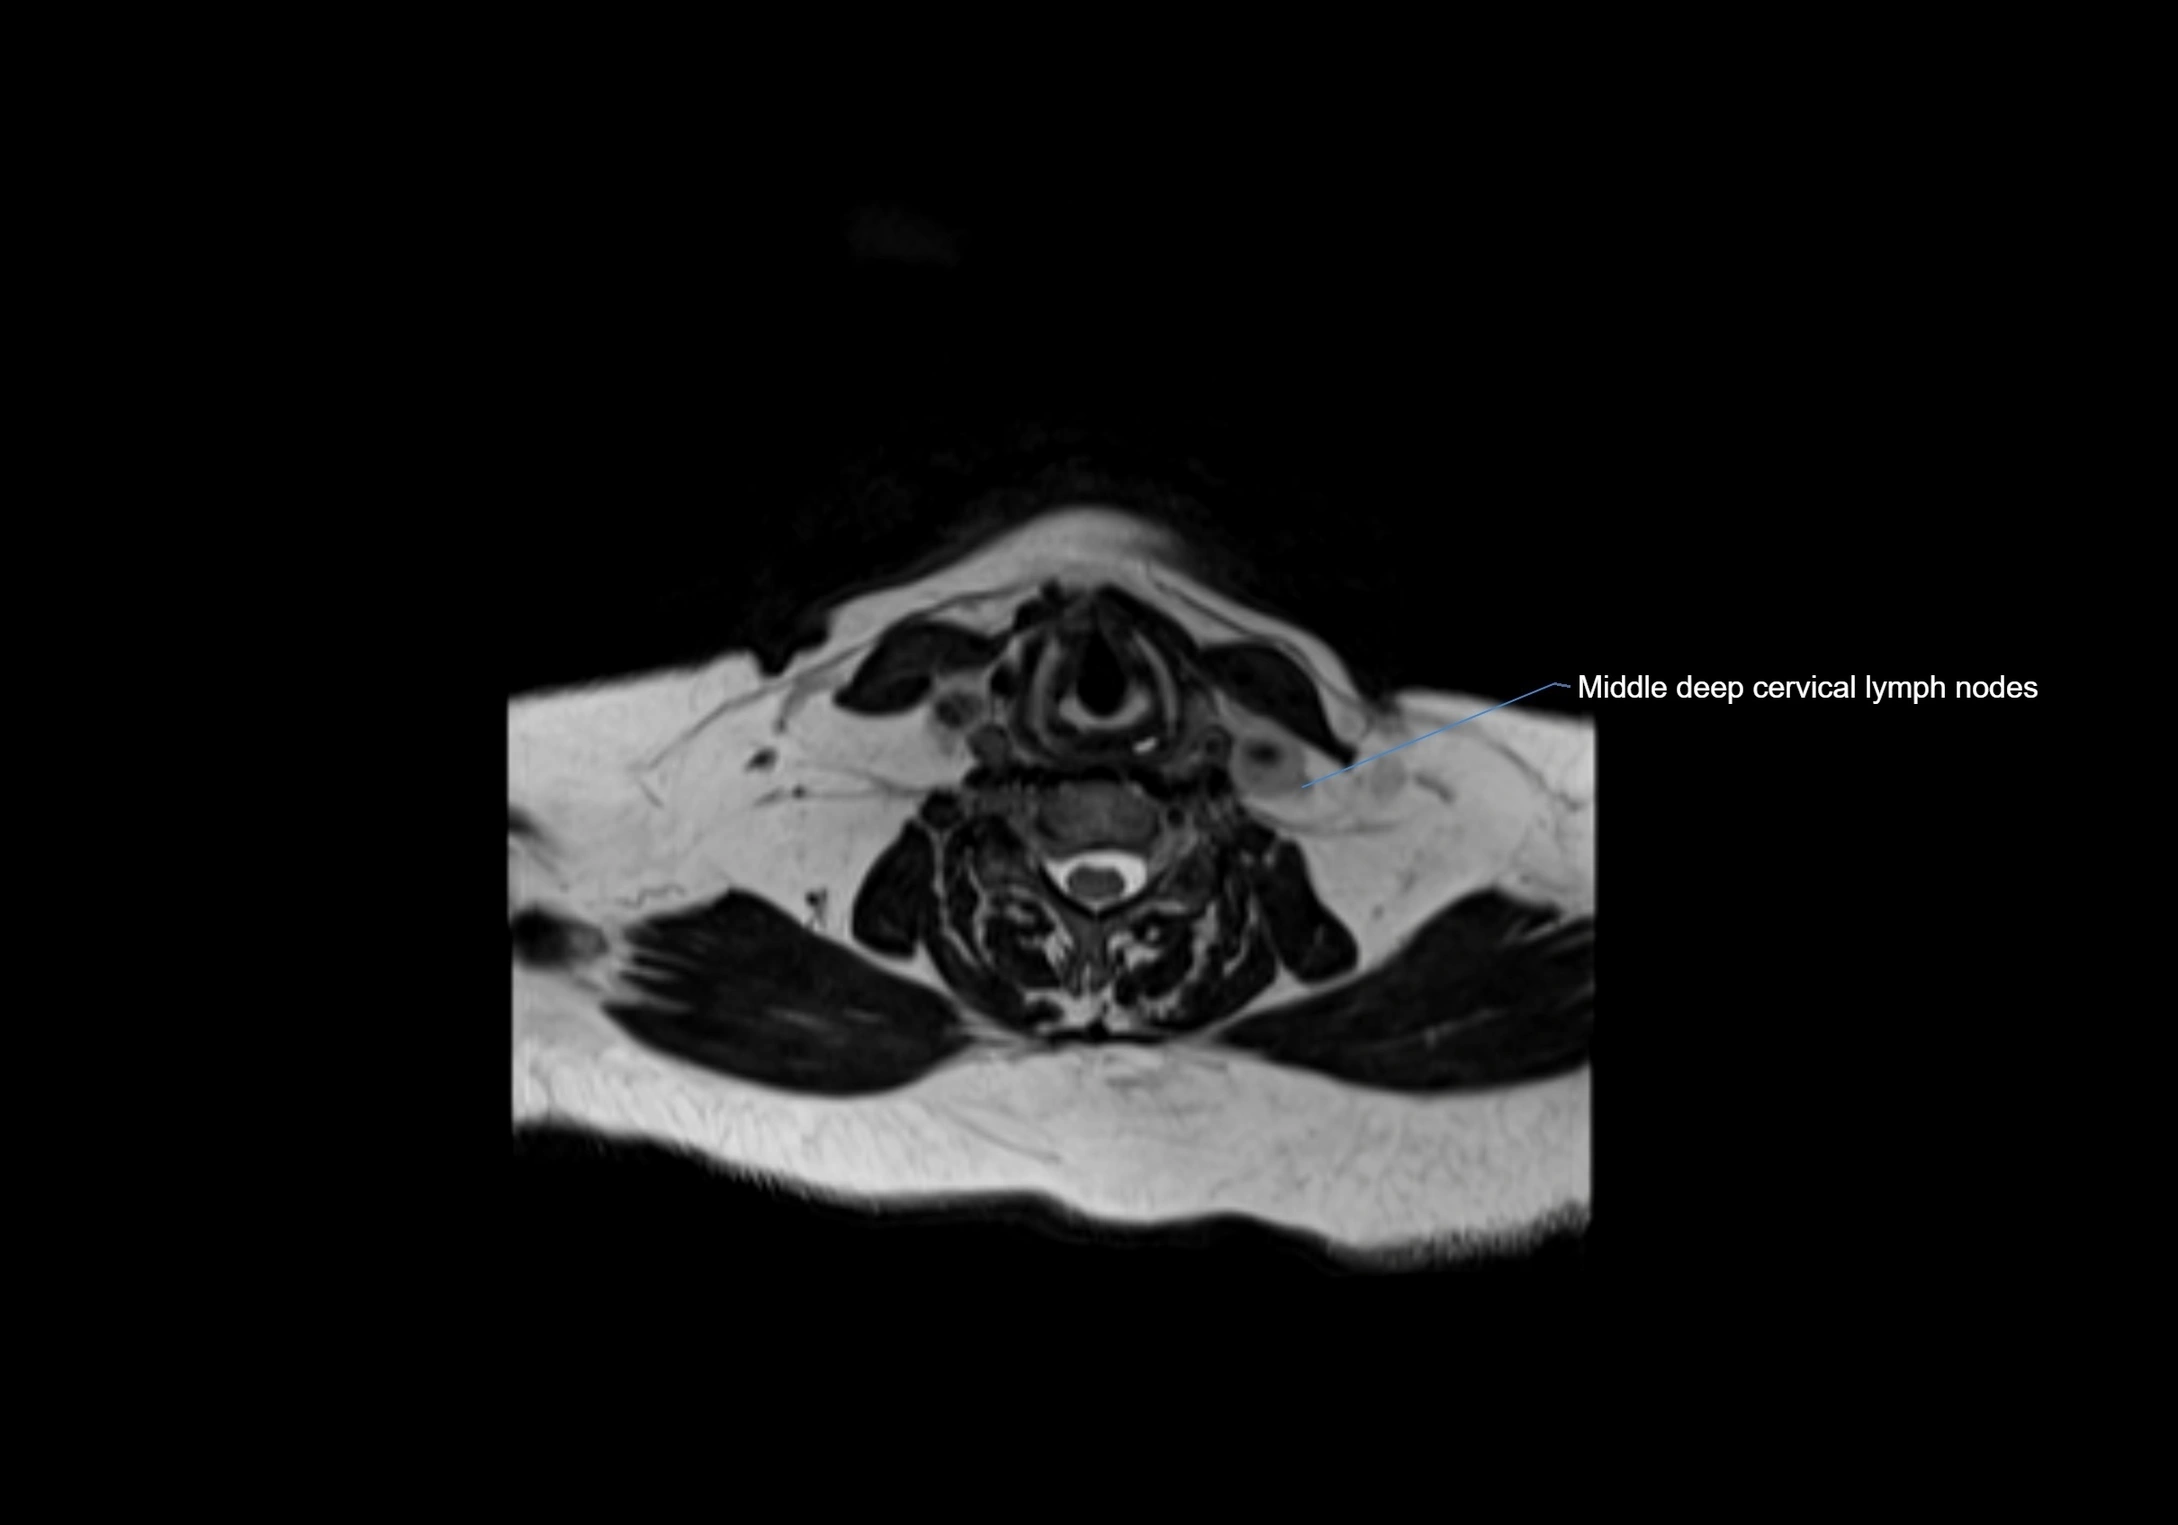

Location

• Found along primary lymph node chains, including preauricular, submandibular, parotid, and occipital regions

• Embedded in subcutaneous fat or superficial fascia, often lateral or posterior to primary nodes

MRI Appearance

T1-weighted images:

• Normal accessory nodes appear as small, oval hypointense to intermediate signal structures within subcutaneous fat

• Surrounded by hyperintense fat, enhancing contrast for visualization

• Pathological nodes may appear enlarged or rounded, sometimes with cortical thickening